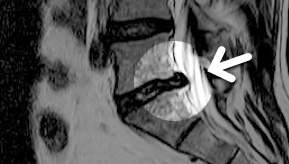

MRI

ϰ ڻ ͼ ̶ ؿ.

ü Ƶ ̰ ȣ µ

㸮 , ٸ ʹ

, Ƹ, ߰ ļ

Ȱ ް

MRI ġ